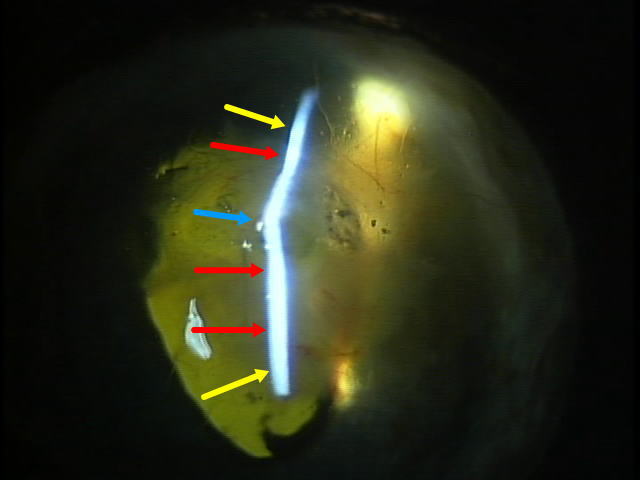

初診時の検眼鏡所見右眼

角膜はボロボロに変性を起こし、ふわふわと浮いている様に見える。眼球中央部分の殆ど全てに障害が及んでいる。

スリットライト所見。黄色の矢印は、眼球のカーブに沿ったもの。赤色の矢印は、眼球中央部分なのに真っ直ぐ。青色の矢印は、飛び出している。青色矢印部分が、最も弱い部分である。